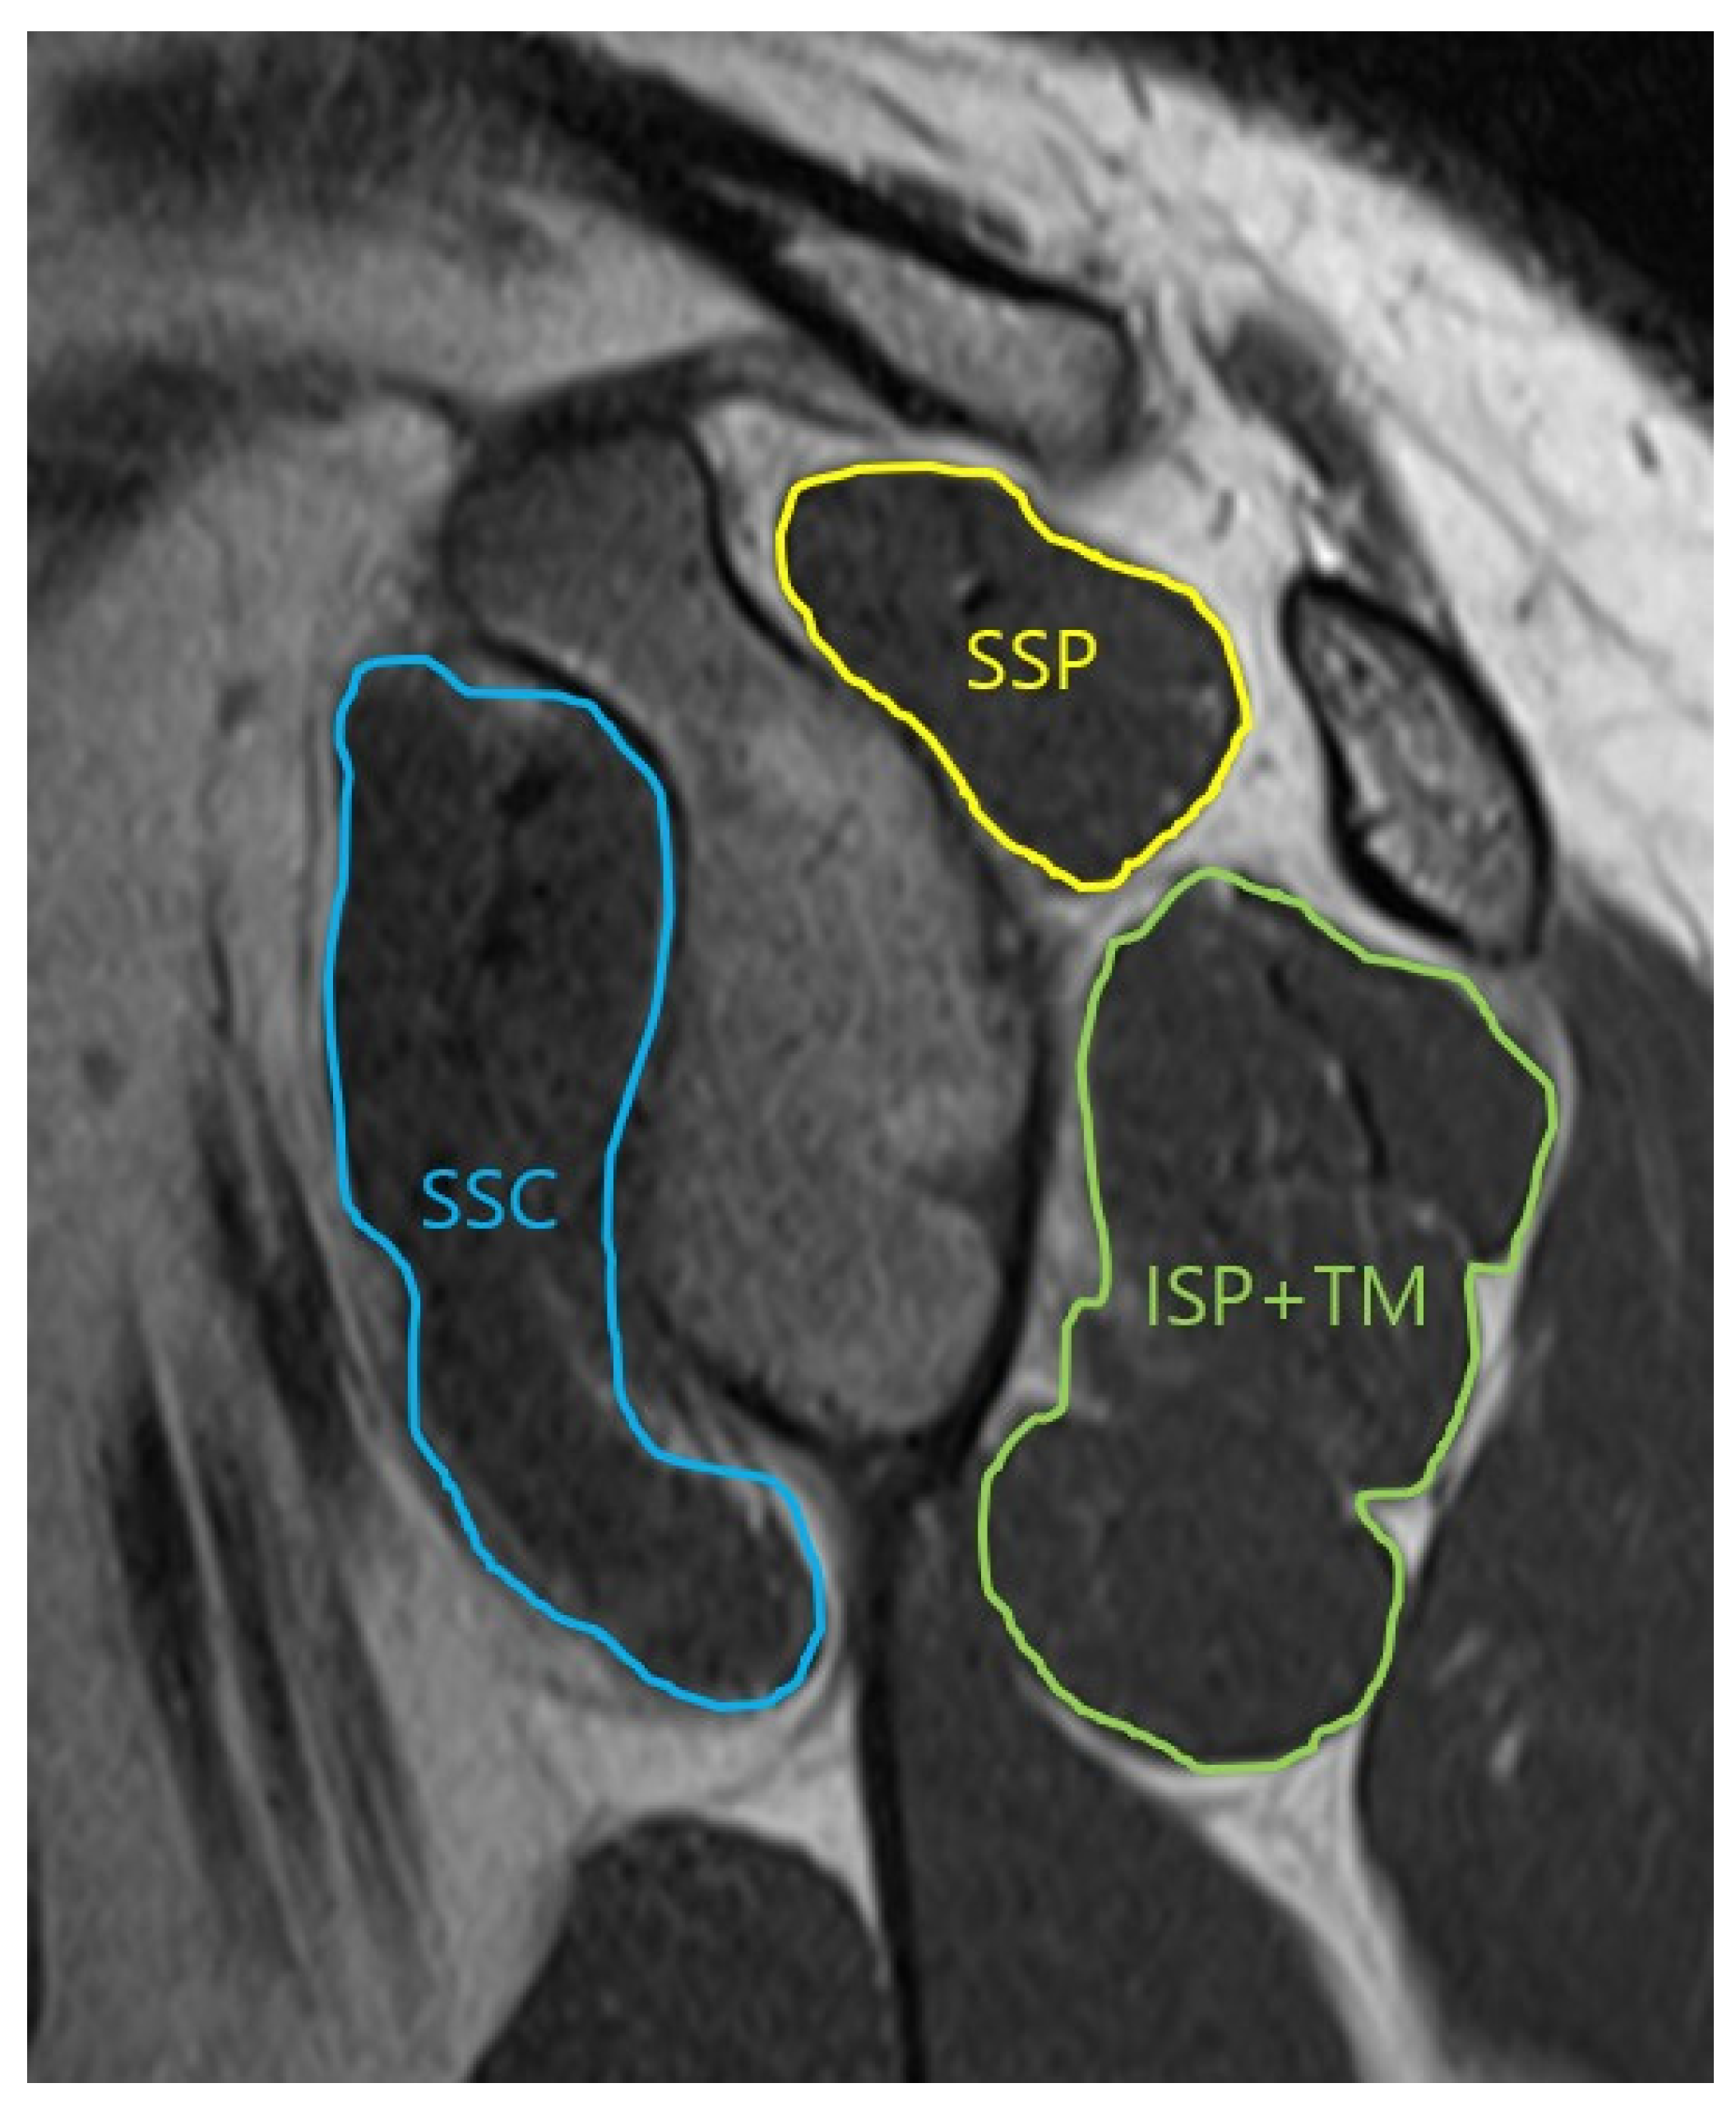

2.2. Muscle Area Measurement

| Glenoid face view SSP | 0.959 | 0.911 | 0.0001 |

| Glenoid face view SSC | 0.901 | 0.899 | 0.0001 |

| Glenoid face view ISP/TM | 0.898 | 0.904 | 0.0001 |